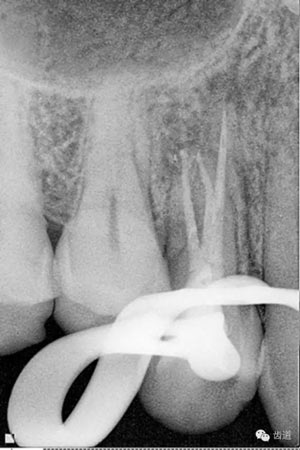

處理:去除暫封物,超聲根管蕩洗,清除氫氧化鈣糊劑,干燥根管,拍片顯示2506牙膠尖適合,根管內(nèi)放置AH plus,熱牙膠連續(xù)波根管充填。

數(shù)碼x攝影顯示:近中頰根及腭根根管充填恰填,遠(yuǎn)中根管有遺漏。

顯微鏡下反復(fù)探查根管,未探及遺漏根管口,放置棉球,zoe暫封。轉(zhuǎn)診上級(jí)醫(yī)生處理。